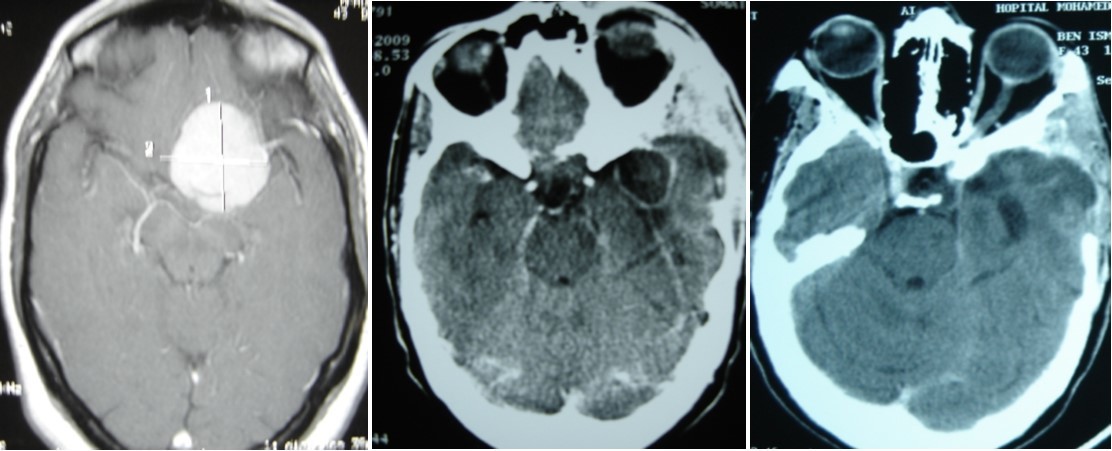

A 47 year old patient with no previous medical history presented with features of raised intracranial pressure, statokinetic cerebellar syndrome as well as left sided hemiparesis. The diagnosis of posterior fossa space occupying lesion was made. Neuroradiologic investigations demonstrated posterior fossa lesions. Magnetic resonance imaging and spectroscopy were in favor of a multiple infective process (Figure 1). Stereotatic biopsy was carried out on the patient and parasitological and histological examinations of the specimen concluded to a filamentous fungal infection of Aspergillus type. Culture and staining techniques categorized the specie as Aspergillus fumigatus (Figure 2).

Figure 1.cerebral MRI axial T1-weighted (A) and coronale (B), showing a multiples well circumscribed posterior fossa lesions

Patient was placed on intra veinous amphotéricin B but this was complicated with acute active hydrocephalus warranting external ventricular drainage (Figure 3). Subsequently, he developped staphylococcal meningitis as day 8 post op, treated with intra veinous vancomycin. Patient developed renal insufficiency and hyperosmolar non ketotic coma for an unknown diabetis for which amphotéricine B therapy was stopped. His neurological status deteriorated with a Glasgow coma scale (GCS)7/15. Posterior fossa surgery was performed with excision of the fungal abscess (Figure 4) and Voriconazol was instituded post operatively for fungal therapy with improvement of the neurological status to GCS 13/15. But the patient succumbed to acute cardiac failure.

Figure 3.cerebral CT scan with axial view showing acute hydrocephalus (A) and control after external ventricular drainage (B)

Figure 4.cerebral CT scan pre operative (A) and post operative (B) after posterior fossa surgery with total removal or abscesses

A 45 year-old woman, operated 6 months before for left sphenoid wing meningoma revealed by raised intracranial pressure, with hemiplegia. She underwent surgery, with simpson I resection. The post operative outcome was good and the patient was discharge. Six months later, she presented a swelling on surgical site of skin incision. Blood check found inflammation with raised C-Reactive Protein. CT scan permitted to suggest brain abcess and she was operated in emergency with bone flap removal and the abscess complete excision. Bacteriologic and Histologic examination of the pus, revealed aspergillus flavius. The patient was treated by amphotéricin B because it was the antifungal avalailable in the hospital officine. Two months treatment was necessary to controle cerebral aspergillosis (Figure 7) and the patient was discharged with good outcome.

Figure 7.(A) pre operative MRI, axial T1 weighted with enhancement of sphenoid wing meningioma. (B) Ct scan showing an brain abscess in post op area. (C) CT scan after remoral sugery and 2 months medical treatment.